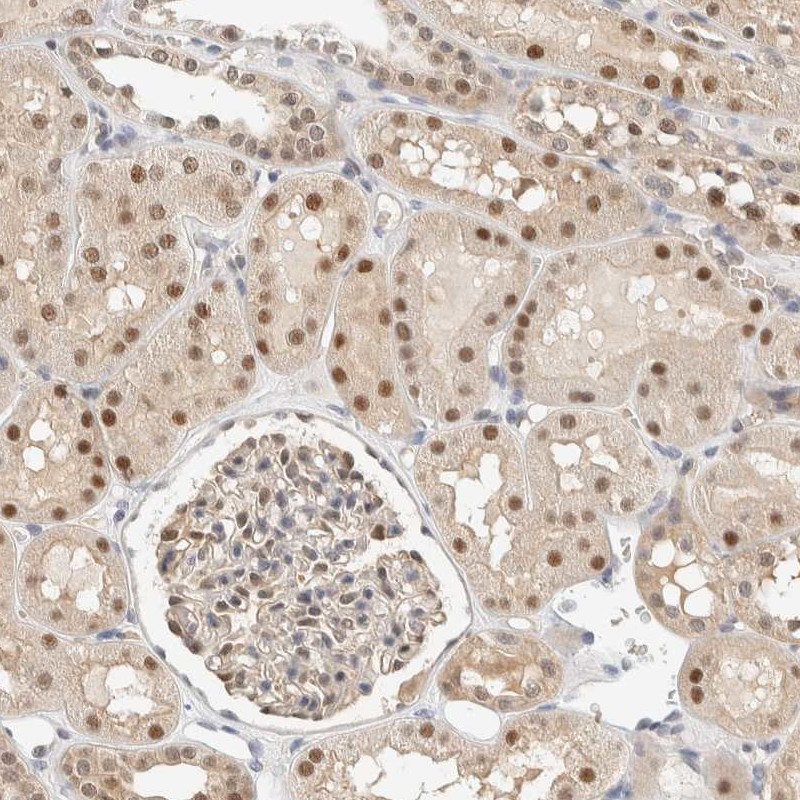

Immunohistochemical staining of human kidney shows nuclear and cytoplasmic positivity in cells in tubules and glomeruli.